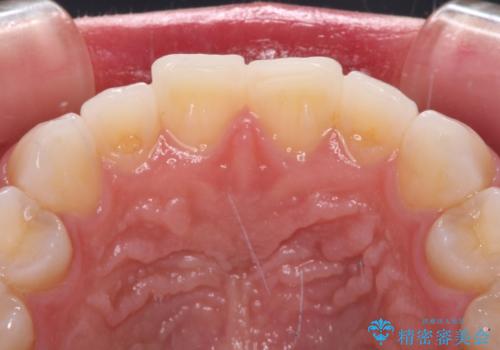

- 矯正治療で歯列を整えた後、前歯の形が気になった患者様です。

矯正前の歯列の影響で、前歯の先端が非対称にすり減ってしまったため、矯正治療後の形が非対称になっていました。

むし歯はなく、矯正治療で咬み合わせが改善していたので、侵襲量の少ないラミネートベニアにて治療することとしました。